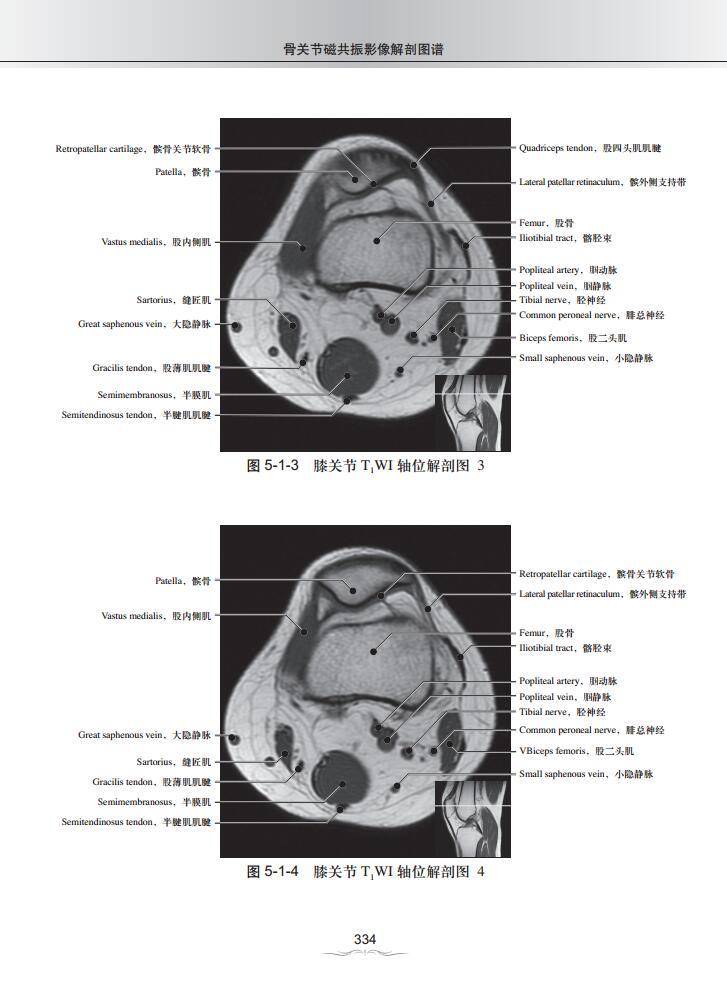

第五章 膝关节MRI影像解剖图谱

一、T1WI轴位解剖图